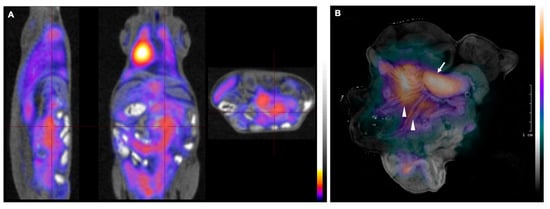

2.2. Successful Monitoring of Lymphoma Expansion in Nodal Metastasis by PET/MR and Subsequent CLI